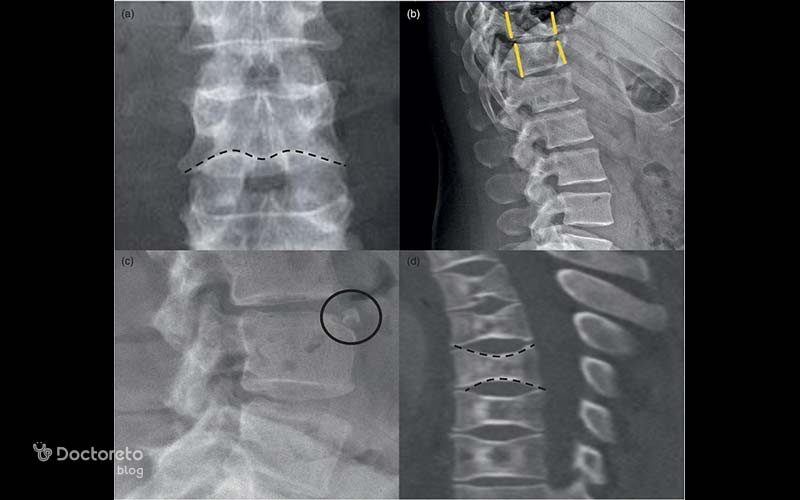

یکی از مشکلات ستون فقرات، پوکی استخوان در این ناحیه است. در عکس پوکی استخوان ستون فقرات میتوان شکستگیهای احتمالی در استخوانها را تشخیص داد. جا به جایی مهرهها، شکستگیهای فشاری و مهرهای و نازک شدن ترابکولاهای افقی در جسم مهرهها، از جمله مواردی است که میتوان در تصاویر به دست آمده از ستون فقرات، از آنها برای تشخیص پوکی استخوان استفاده کرد.